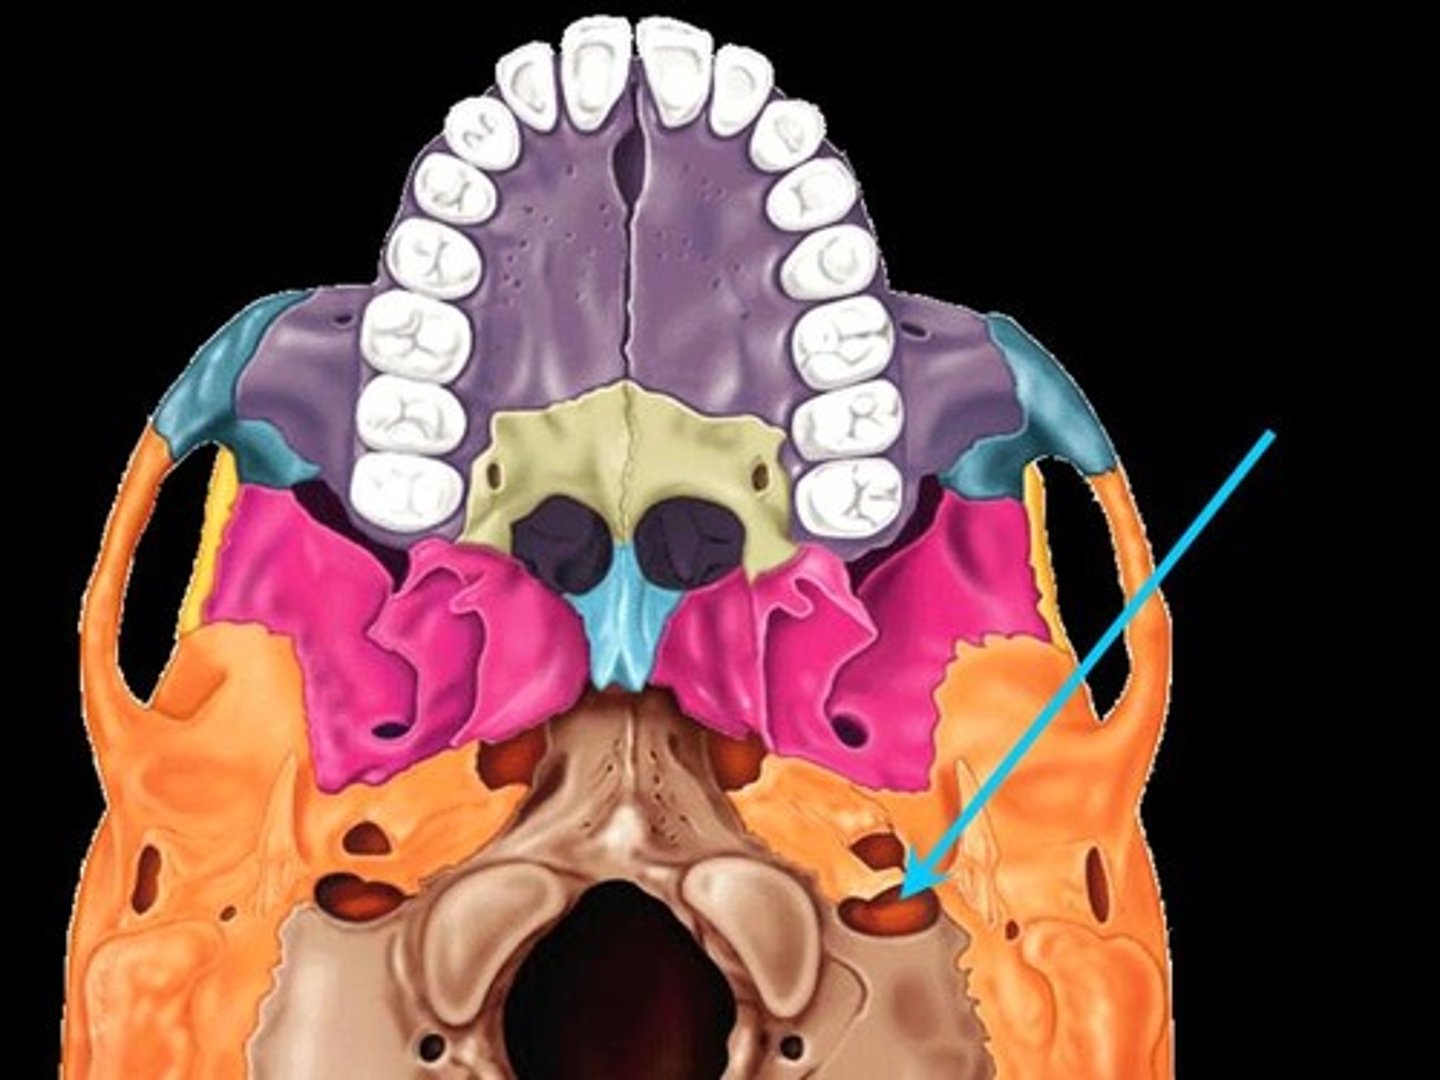

Jugular foramen

Jugular foramen

Carotid canal

Occipital condyles

Foramen magnum

Hypoglossal canal

Foramen ovale

Greater wings

Less wings